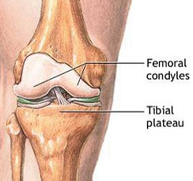

La articulación de la rodilla está formada por las partes inferior del fémur, superior de la tibia y posterior de la rótula actuando como una gran bisagra. Es la articulación más lesionada en el deportista y su tratamiento exige un gran conocimiento de la anatomía así como de la cirugía traumatológica, protésica y artroscópica.

Fracturas del tercio superior de la tibia

Las fracturas en el tercio superior de la tibia suponen el 1% de todas las fracturas y el 8% de las fracturas del anciano. Están causadas por fuerzas violentas que producen desviaciones laterales sobre la rodilla. La osteoporosis en el paciente de edad facilita estas fracturas. Son lesiones que también vemos en el ámbito deportivo fundamentalmente en aquellos deportes que exigen un sobreesfuerzo de la articulación de la rodilla como el esquí, el fútbol o el patinaje. En los deportistas suelen acompañarse, además, de lesiones ligamentosas que pueden pasar desapercibidas si no se realiza una exploración exhaustiva.

El tratamiento de las fracturas del tercio superior de tibia es quirúrgico con la finalidad de devolver a la rodilla su anatomía normal para el rápido inicio de la movilidad articular. Los avances en técnica artroscópica y los nuevos implantes permiten el tratamiento de estas fracturas de una forma poco agresiva y fiable que disminuye las complicaciones postoperatorias y agiliza el tiempo de recuperación.